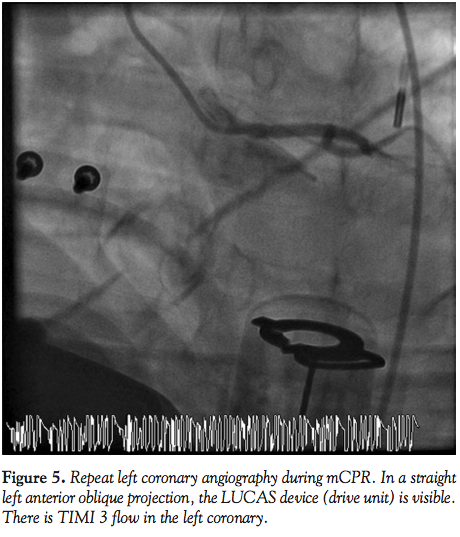

Case 5. A 57-year-old female with a history of diabetes mellitus, hypertension, and hyperlipidemia presented with a 3-month history of exertional angina. A diagnostic angiogram demonstrated a calcified 80% lesion in the mid left anterior descending (LAD) artery and 70% proximal circumflex lesion. The patient was referred to our institution for PCI. Her PCI was complicated by stent embolization and dissection of the proximal LAD and circumflex. The patient developed severe chest pain and angiography demonstrated TIMI 1 flow in the

LAD (Figure 9). The patient suffered cardiac arrest with recurrent ventricular fibrillation requiring defibrillation 15 times. Mechanical CPR was initiated and continued during 30 minutes of persistent cardiac arrest while an IABP was placed and PCI of the LAD and circumflex were performed (Figure 10). TIMI 3 flow was achieved after placing 2 drug-eluting stents from the proximal to mid LAD and an additional stent in the circumflex. The patient regained spontaneous circulation with minimal pressor support and she was transferred to the CCU. Her condition improved and both the vasopressor and IABP were discontinued the following day. On hospital day 4, the patient was discharged home without any sequelae.

Fluoroscopic and cineangiographic imaging during mCPR with the LUCAS device requires few significant adjustments. The images presented here represent one center’s experience and diagnostic images were obtained in all cases. Anterior-posterior projections are limited by the height and radio-opacity of the LUCAS drive unit over the patient’s chest. Straight right and left anterior oblique views provide adequate visualization despite the back-brace component of the device being visible on fluoroscopy. As evidenced in Cases 1 and 4, significant cranial angulation (>30°) can provide coronary imaging without visual encroachment by the device components.

In animal models, cerebral blood flow during CPR is improved with mCPR,15 and mCPR devices provide significantly higher coronary perfusion pressures than manual CPR.16 Coronary flow assessment has been reported in both animal models and human subjects.16,17 In 4 out of 6 patients studied by Larsen et al with TIMI 3 flow during mCPR, invasive measurements documented adequate coronary perfusion pressure gradients. In the present experience, coronary flow during mCPR is pulsatile, but classification by TIMI grade is readily apparent. In Cases 1, 4, and 5, the PCI procedure itself was performed during mCPR compressions (Figures 1, 2, 8, and 10).